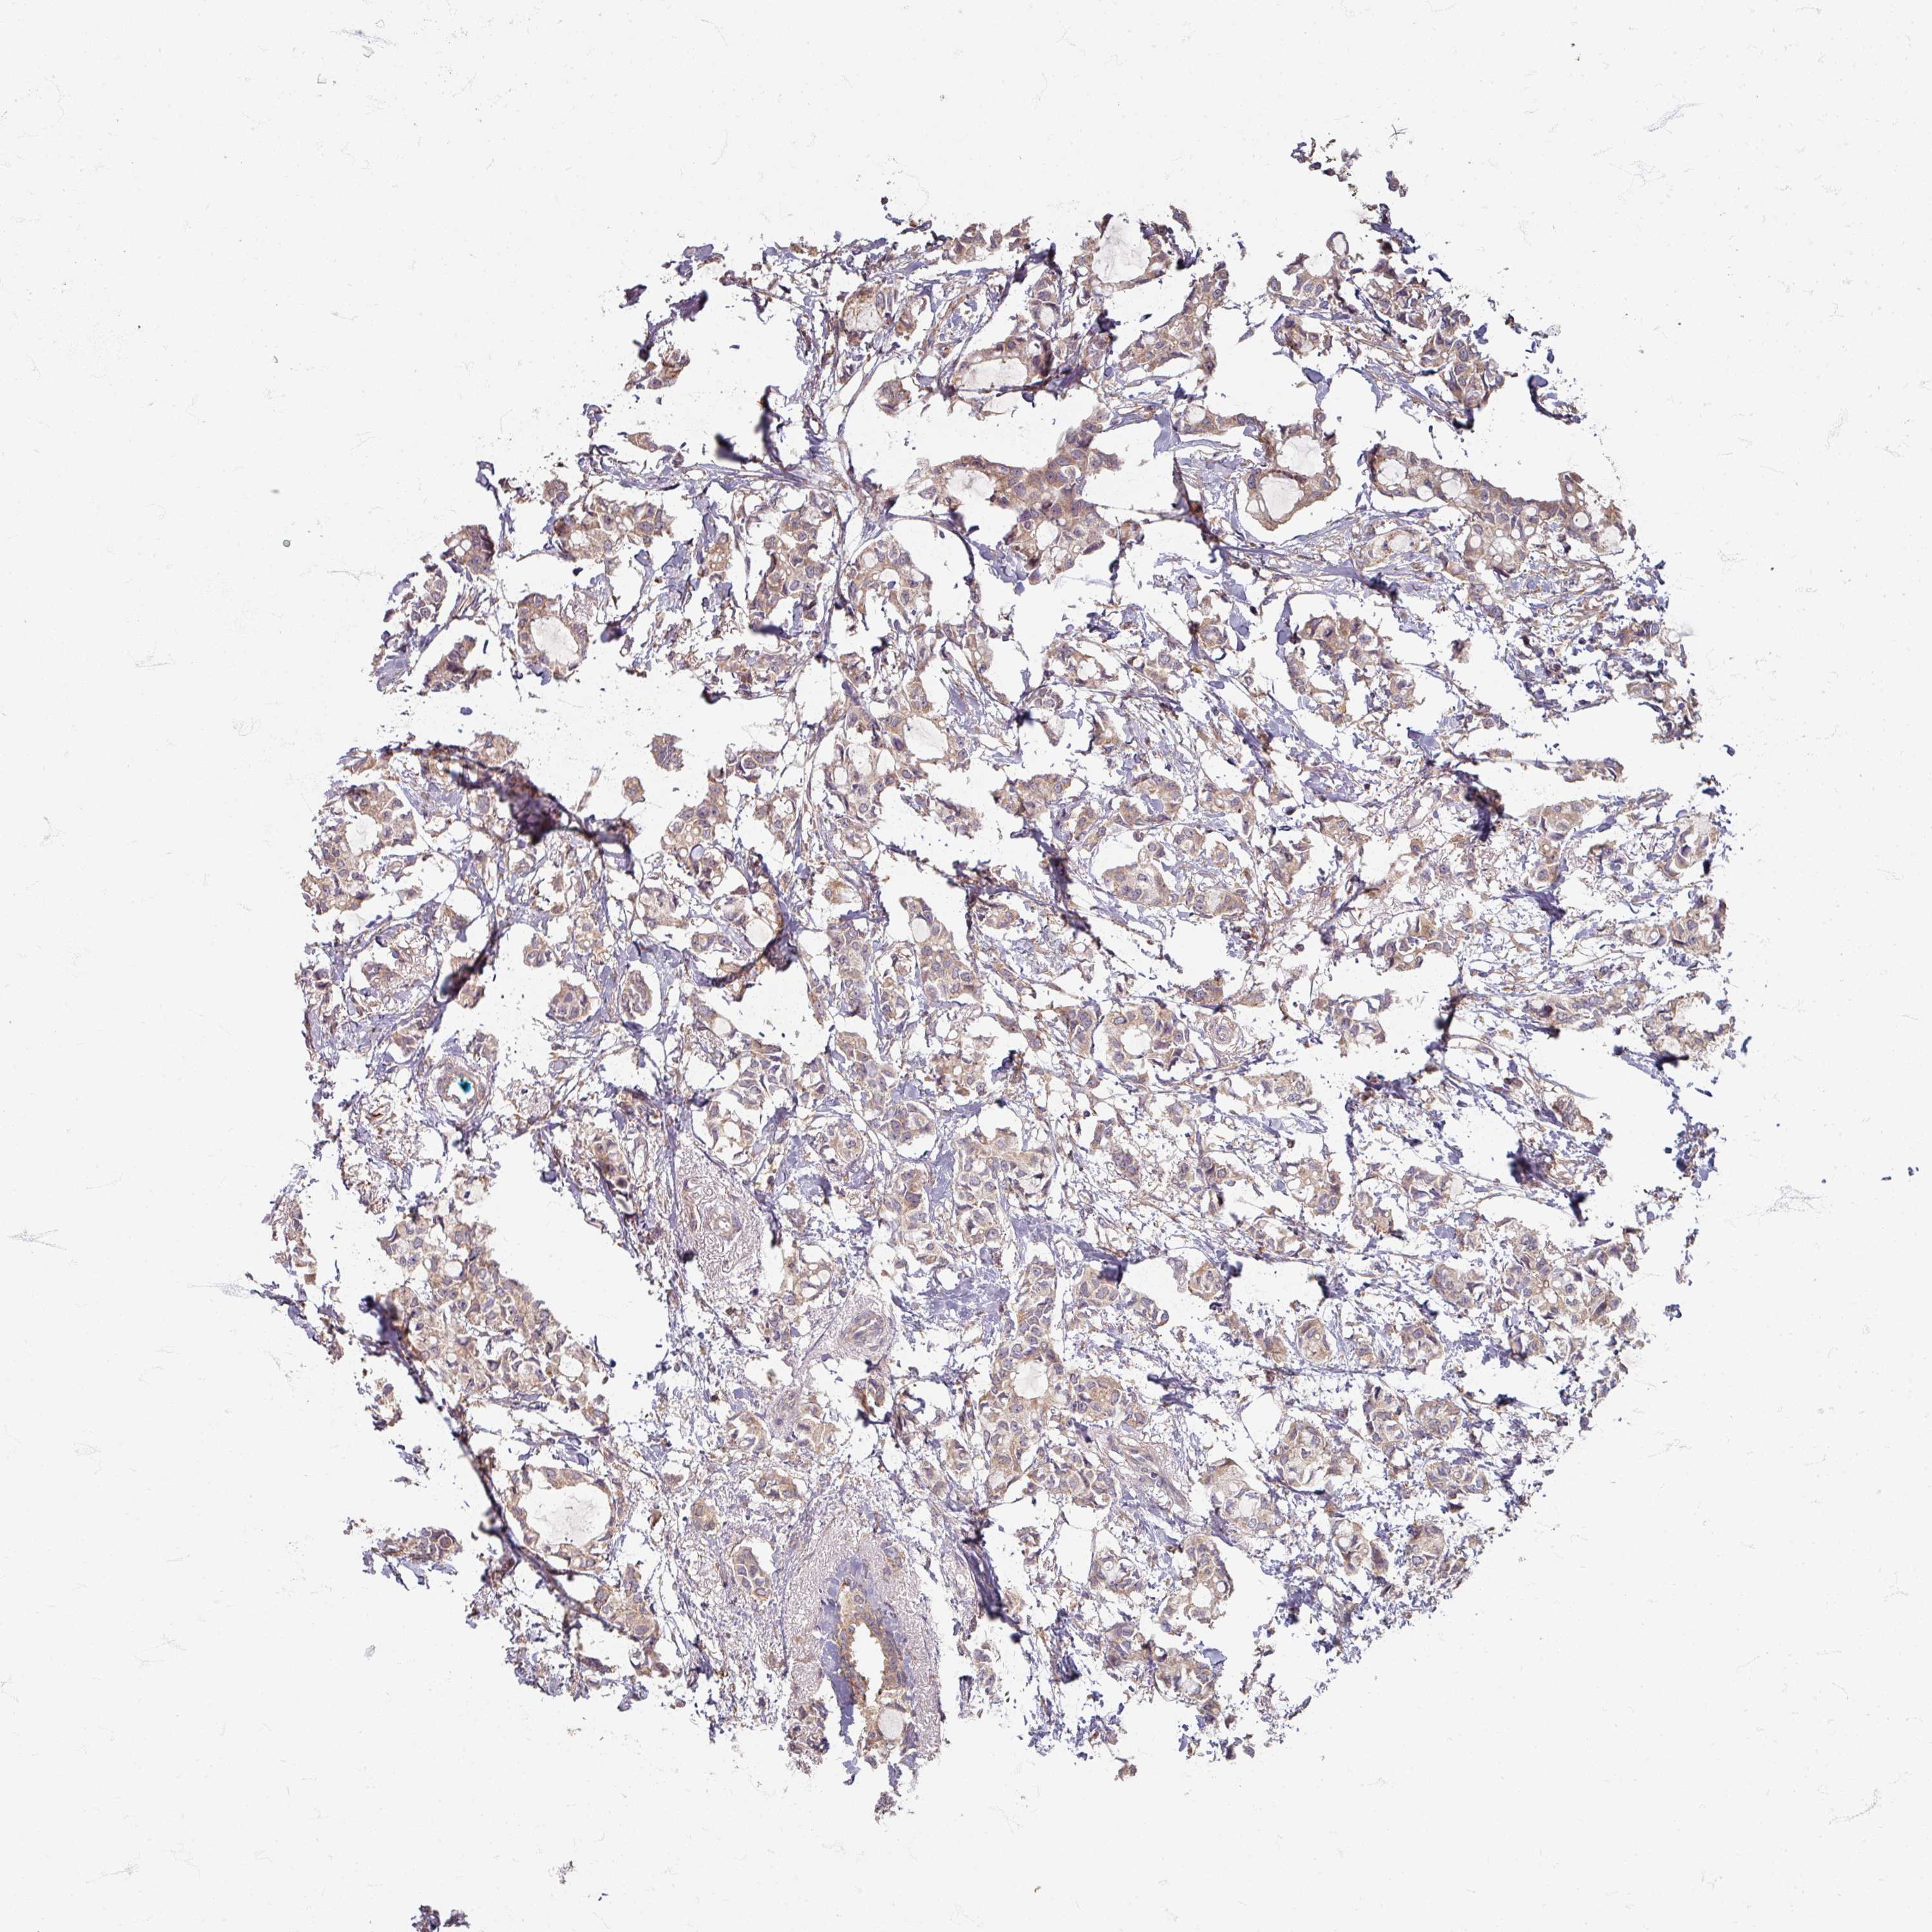

CANCER BREAST CANCER Show tissue menu

BRCA TCGA BRCA VALIDATION PROTEIN EXPRESSION